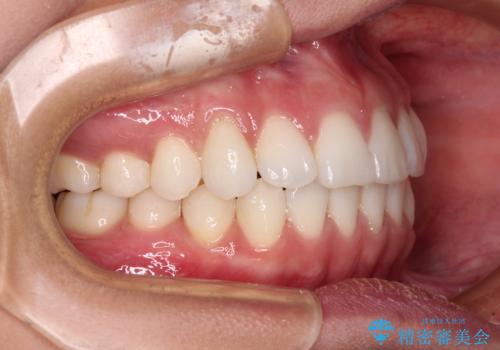

【モニター】インビザラインで口を閉じやすく

- 前に出ている上顎前歯が気になるとのことで来院された患者様です。

インビザラインを用い、IPR(歯と歯の間を削る)と歯列全体を後方に移動させることで、可能な限り前歯の突出感を改善することとしました。

元々の歯列も整っており、横顔の印象の出っ歯ではなかったため、仕上がりに満足できない可能性があると心配しておりましたが、口が閉じやすくなり、患者様には大変満足していただきました。